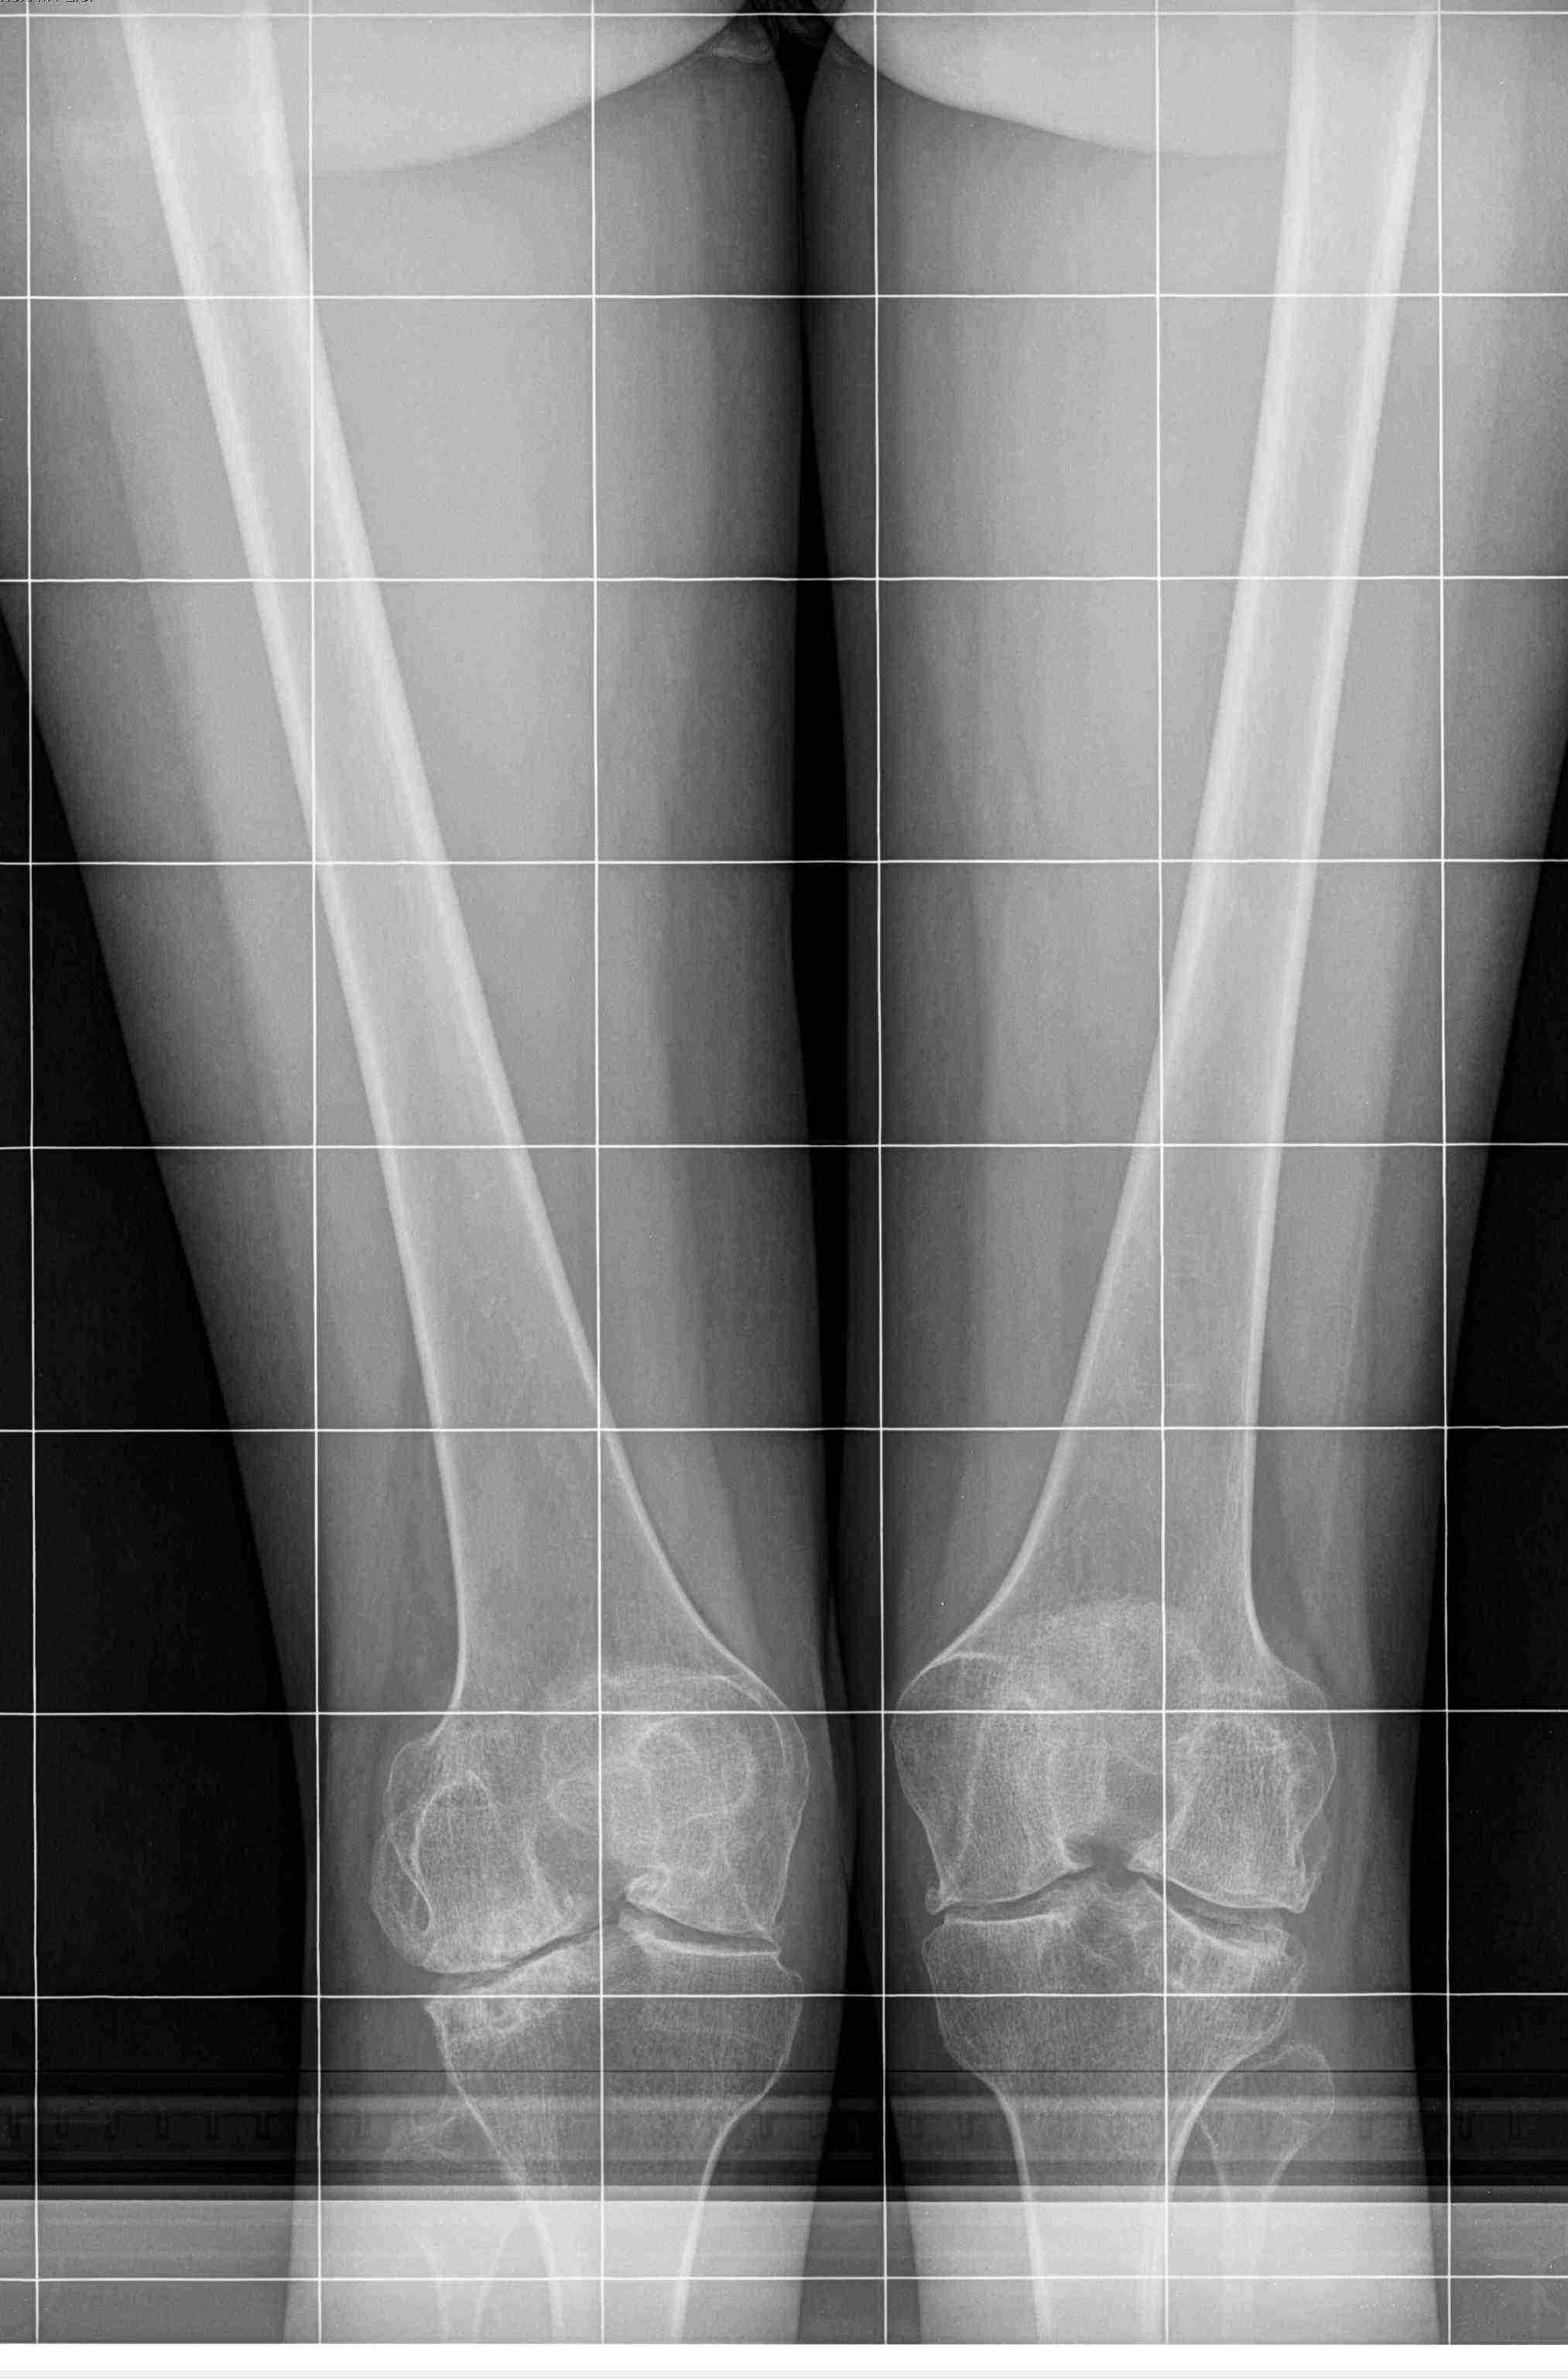

[Ortho] вальгусная деформация колена на фоне РА

девушка 29 лет с ревматоидным артритом, социальная, лечение получает.

вальгусную деформацию на уровне коленных суставов замечает около 10 лет,

прогрессирует. Движения в правом коленном суставе:разгибание полное,

сгибание около 95-100 град. Боли особой нет. Консультировалась в